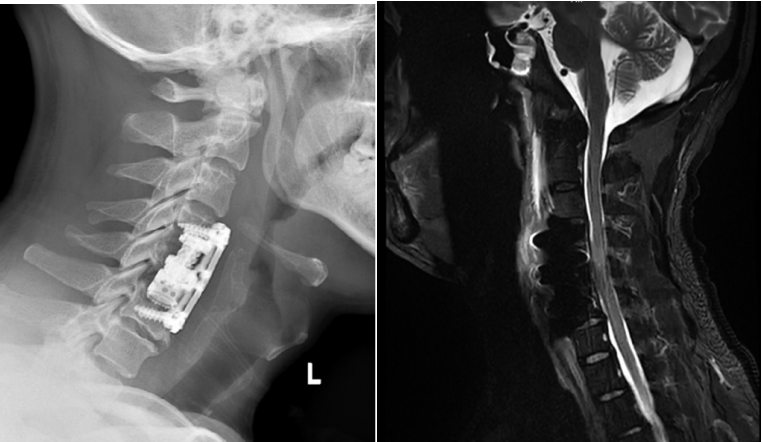

手術后患者X光及核磁共振復查

“手術核心操作用了不到一個小時,新型錐體植入完成后,X光報告人工椎體安得非常好,整個手術室都響起了掌聲。”負責此次手術第二助手的蔣奎軍醫生回憶起當時的場景,仍難掩激動。